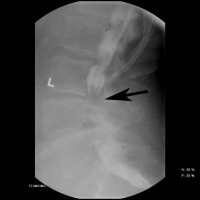

(Click to Enlarge Image) This illustration demonstrates the change in the diameter in the canal in a patient with spinal stenosis. The picture on the right shows the canal wide open with flexion (bending forward). The picture on the left shows significant compression of the nerve sac in the canal (arrow) with backwards bending. Standing and walking require backwards bending, so the symptoms of central stenosis occur with walking and standing.